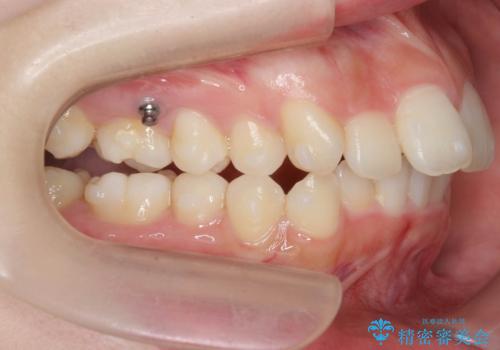

途中顎位が変わり、マイクロインプラントを併用した上顎臼歯の遠心移動が必要となったため治療が長期化しました。